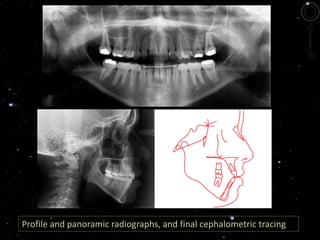

Profile and panoramic radiographs, and final cephalometric tracing

Profile and panoramicradiographs, and final cephalometric tracing